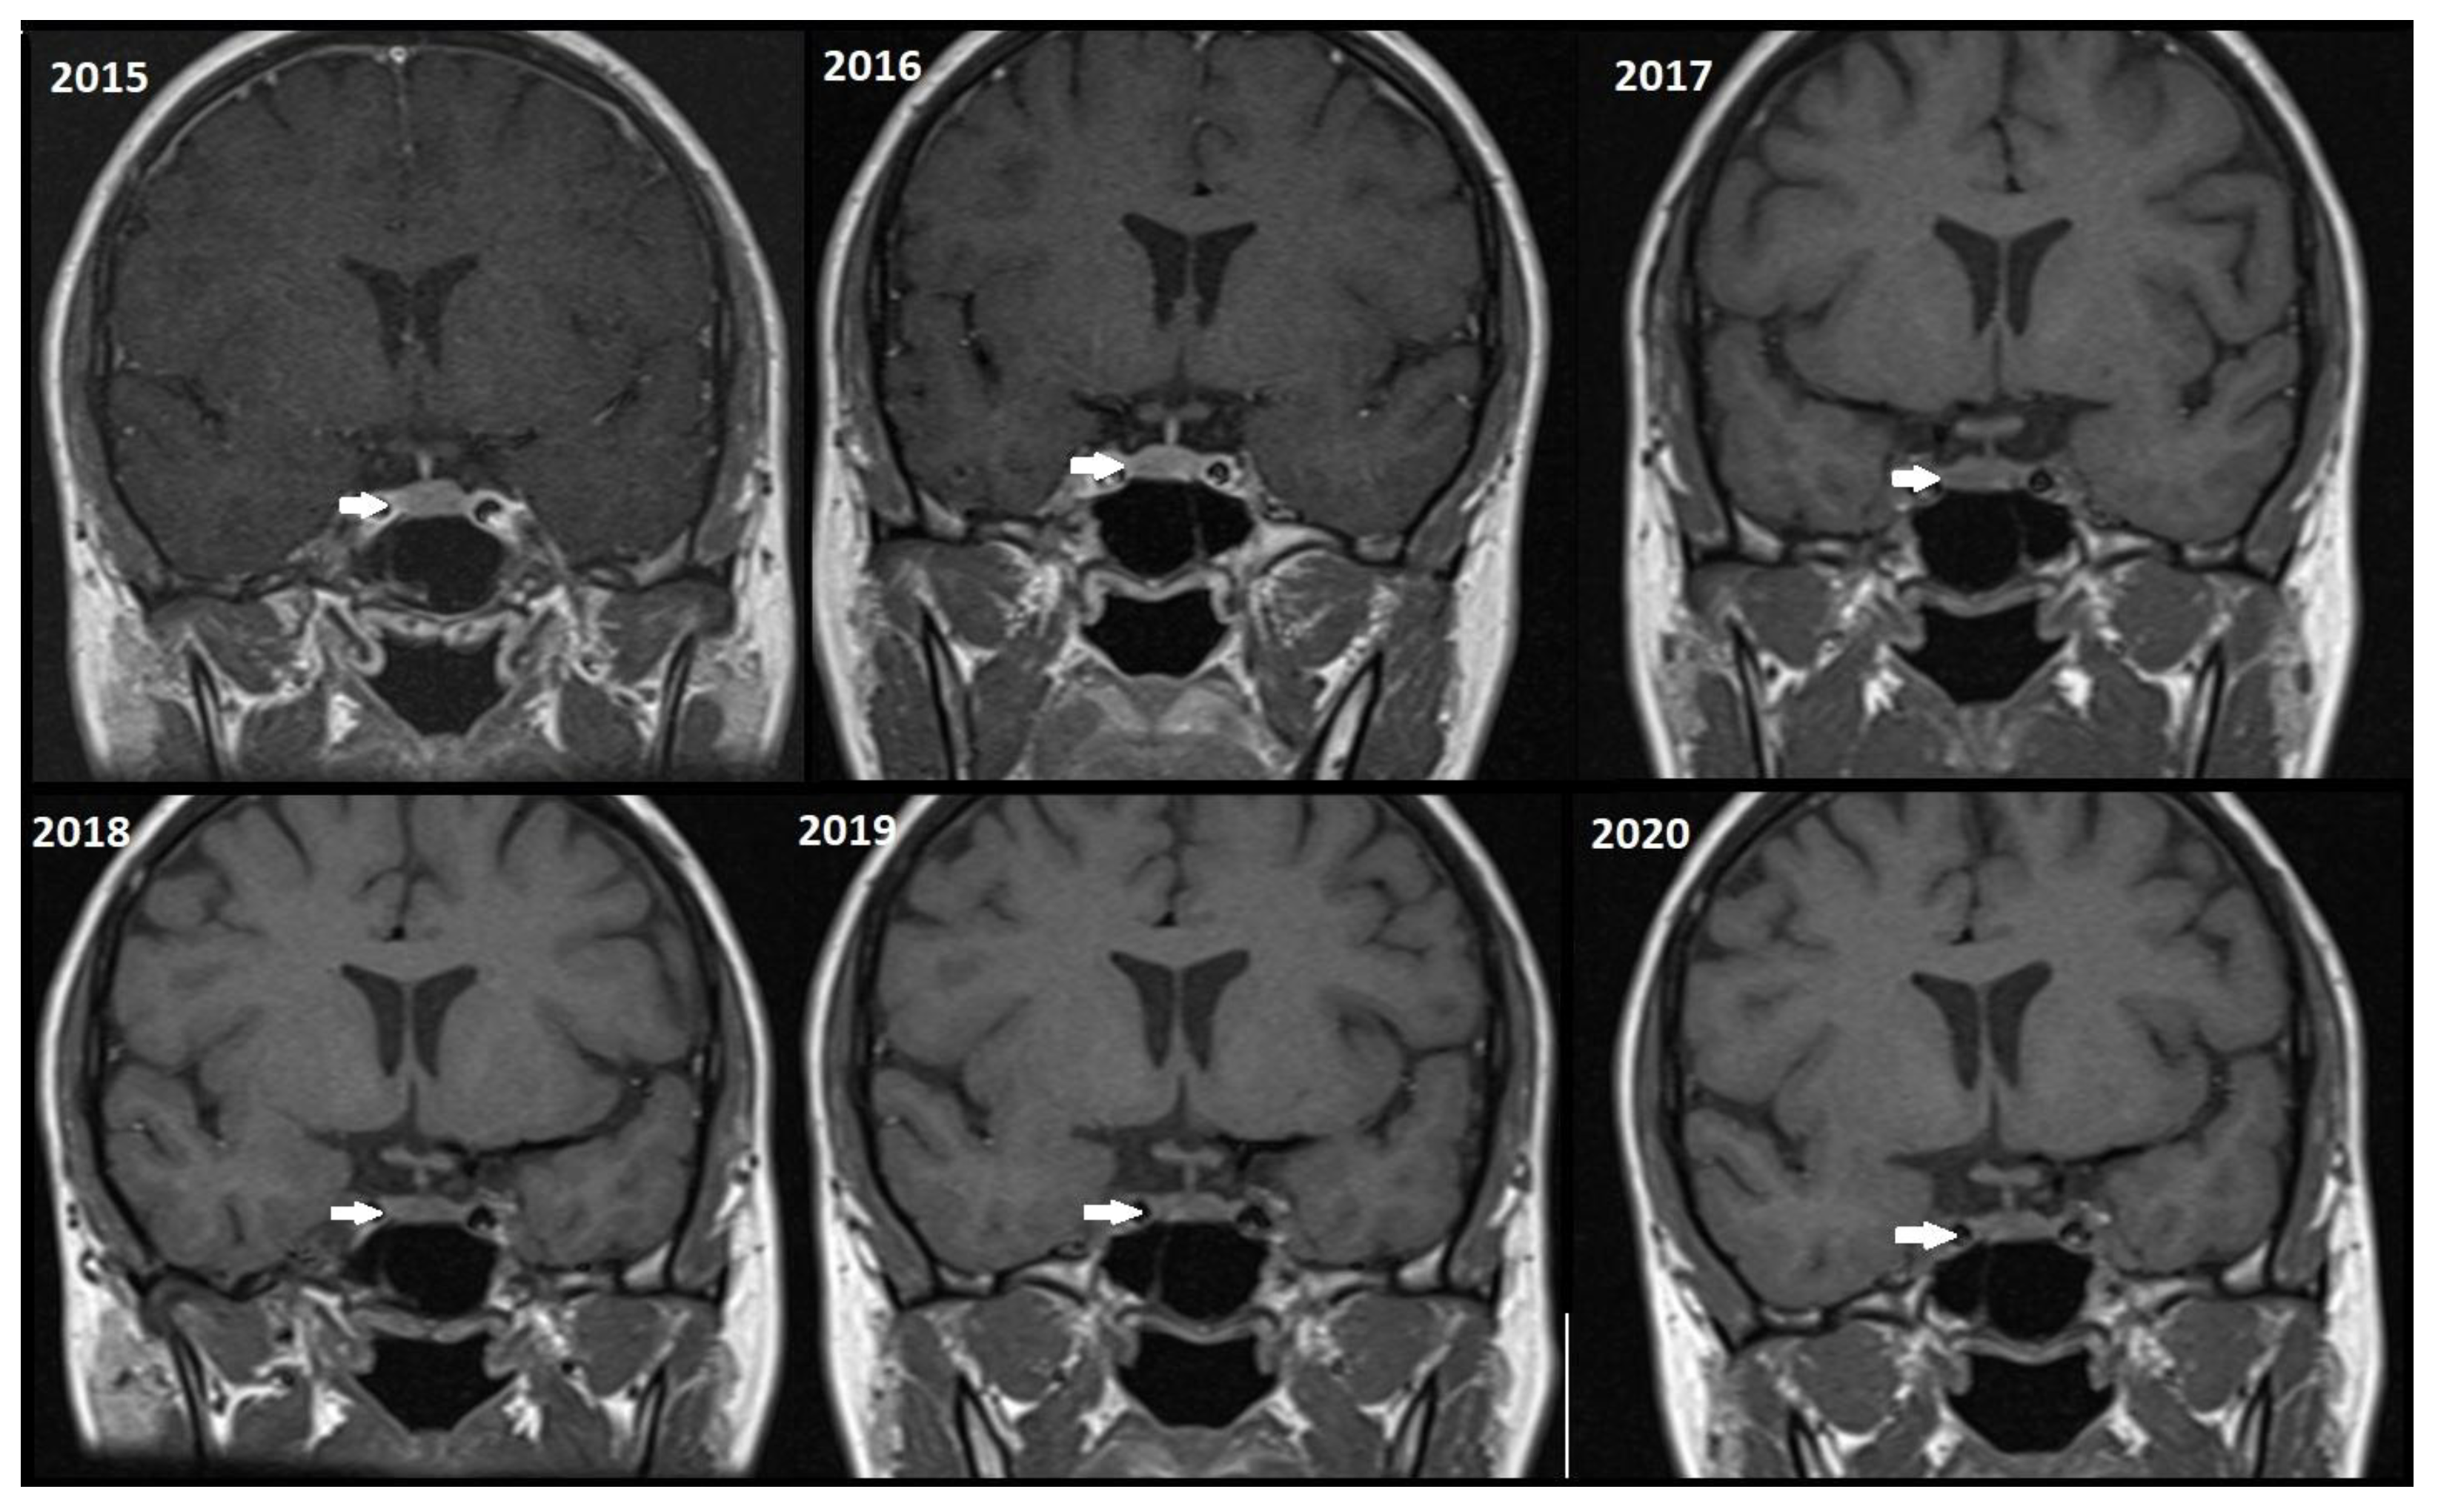

Although, the main cohort contained patients referred between 2020 and 2024, Figure 2, Figure 3 and Figure 4 shows a representative case with historical scans (2015–2020), retrieved from PACS, to demonstrate temporal stability. No evidence of recurrence of tumors in any of the nine who underwent resection of macroadenomas during this period was seen.

Figure 4.

Representative T2W coronal images (2015–2020) of a stable microadenoma (arrows) of a 33 Y/O woman. In the 5 years of follow-up, no size change can be seen.